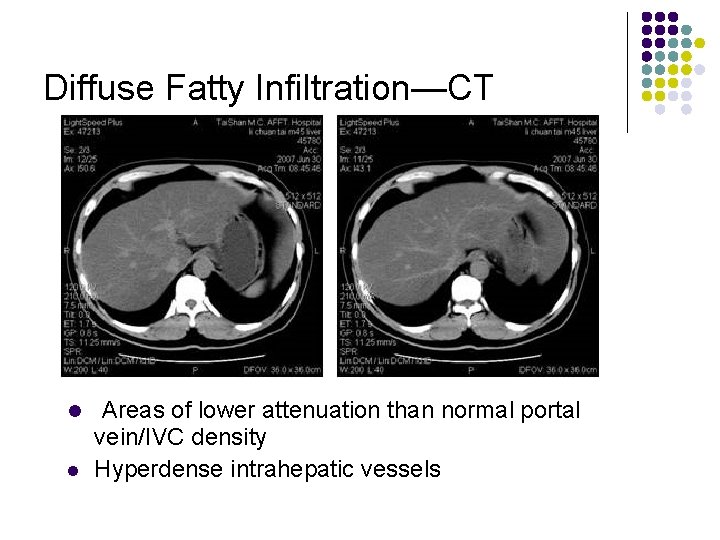

Diffuse Fatty Infiltration—CT l l l Areas of lower attenuation than normal portal vein/IVC density Reversal of liver spleen density relationship (liver density is normal 612 HU greater than spleen) Hyperdense intrahepatic vessels

Diffuse Fatty Infiltration—CT l l Areas of lower attenuation than normal portal vein/IVC density Hyperdense intrahepatic vessels